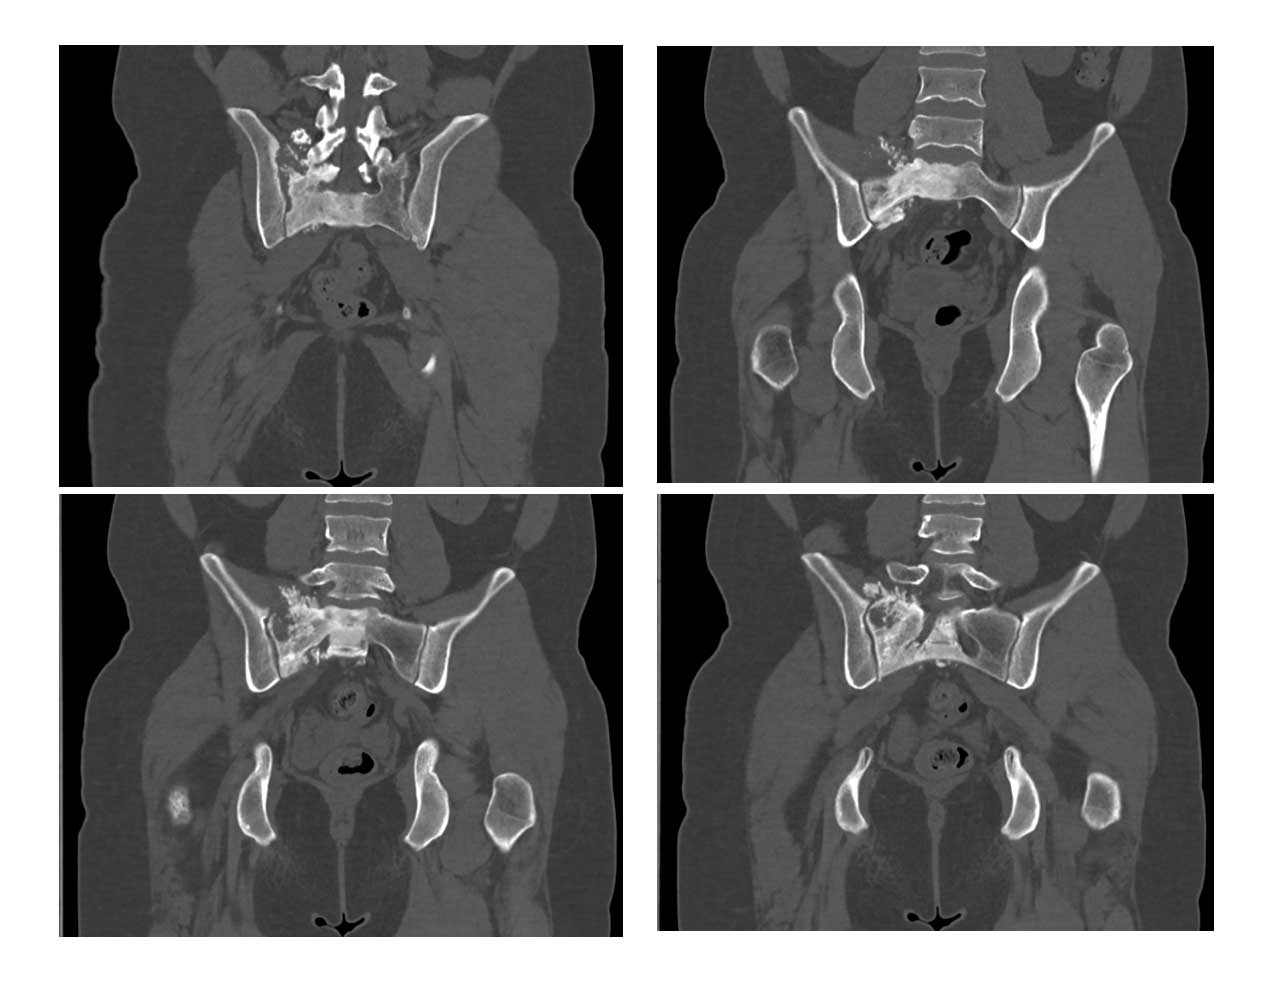

Ameliyat öncesi: Tomografide sağ sakroiliak bölgede düzensizlik ve sklerozun eşlik ettiği tümör dokusu görülmekte.

Ameliyat öncesi:Tomografide sağ sakroiliak bölgede düzensizlik ve sklerozun eşlik ettiği tümör dokusu görülmekte.